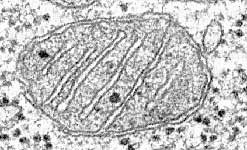

|  |  | | Mitochondrial DNA

Mitochondrial DNA has recently been linked to a range of illnesses from chronic brain disease in children to high blood pressure later in life.

Now scientists at Newcastle University hope that implanting the nucleus of an embryo with defective mitochondria, into an egg from another woman could stop these diseases from being inherited.